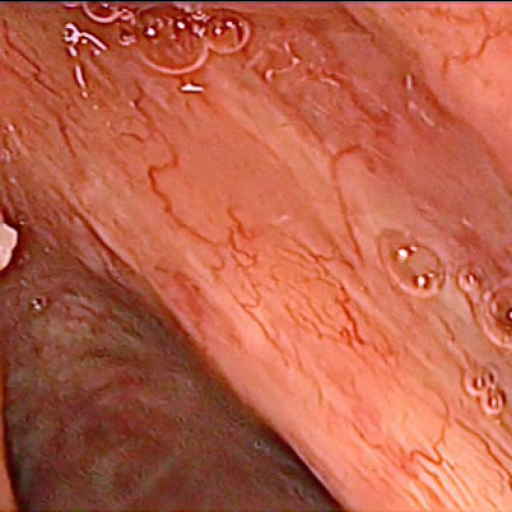

All subsequently described models are trained and evaluated on a dataset, containing 536 manually segmented in vivo color images of the larynx during two different resection surgeries with a resolution of pixels. The images have been captured with a stereo endoscope (VSii, Visionsense, Petach-Tikva, Israel) in an in vivo laryngeal surgery and have been used in prior studies schoob2016 . They are categorized in the 7 different classes void, vocal folds, other tissue, glottal space, pathology, surgical tool and intubation with indices {0, 1, 2, 3, 4, 5, 6}, respectively, which is represented by the gray values of the label maps (see Fig 1). The dataset consists of 5 different sequences from two patients (named SEQ1–4 from patient 1 and SEQ5–8 from patient 2). The sequences have following characteristics:

SEQ1: pre-operative with clearly visible tumor on vocal fold, changes in translation, rotation, scale, no instruments visible, without intubation

SEQ2: pre-operative with clearly visible tumor, visible instruments, changes in translation and scale, with intubation

SEQ3–4: post-operative with removed tumor, damaged tissue, changes in translation and scale, with intubation

SEQ5–7: pre-operative with instruments manipulating and grasping the vocal folds, changes in translation and scale, with intubation

SEQ8: post-operative with blood on vocal folds, instruments and surgical dressing, with intubation

Subsequent images have a temporal contiguity as they are sampled uniformly from videos. To reduce inter-frame correlation, images were extracted from the original videos only once per second. In the comparative study SEQ4–SEQ6 were not used due to high similarity to SEQ3 and SEQ7 respectively, as they do not offer any additional variance to the dataset. Segmentations have been manually created on a pen display (DTK-2241, K. K. Wacom). Figure 2 shows the distribution of the annotated pixels per class. The dataset is publicly available111https://github.com/imesluh/vocalfolds and will be extended in the future.